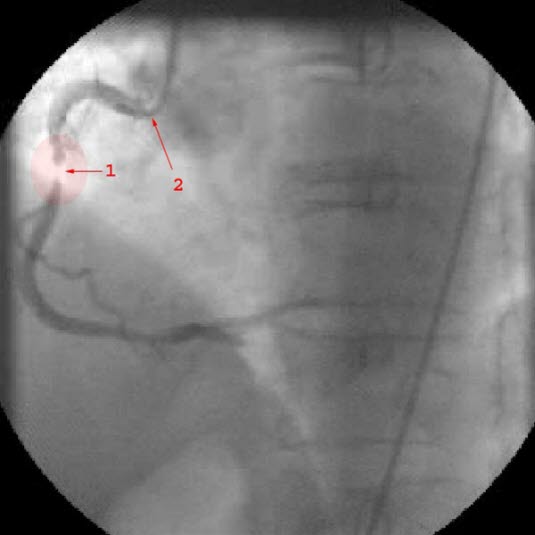

Diagnosen bygger i all hovedsak på sykehistorien. Det vil si de symptomer og tegn som du selv merker. Ved raskt økende brystsmerter av den beskrevne typen bør du ta kontakt med lege snart. Som regel vil det være aktuelt å legge deg inn på sykehus til observasjon og behandling. EKG og blodprøver vil avklare om det er angina eller om det er oppstått et akutt hjerteinfarkt. I de fleste tilfeller vil det være aktuelt å ta bilder av koronararteriene dine i forbindelse med hjertekateterisering (se video nedenfor).

Tidlig etter innkomsten vil legene vurdere om du bør få utført utblokking av koronararterien(e) som er blitt trange - inngrepet kalles perkutan koronar intervensjon (PCI). Andre betegnelser er hjertekateterisering eller koronar angioplastikk. Jo høyere legene vurderer din risiko for alvorlig sykdom og forløp, jo riktigere er det å gjøre PCI. Helst vil man gjøre det innen 12-24 timer.

Ved PCI føres et kateter inn i den trange blodåren, åren vides ut og i de fleste tilfeller setter man inn en stent. Stent er en type armering som skal forebygge at blodåren raskt lukker seg igjen. Andre ganger kan det bli nødvendig med en åpen hjerteoperasjon der man syr inn en ny blodåre forbi den eller de årene som er trange (bypass-operasjon).